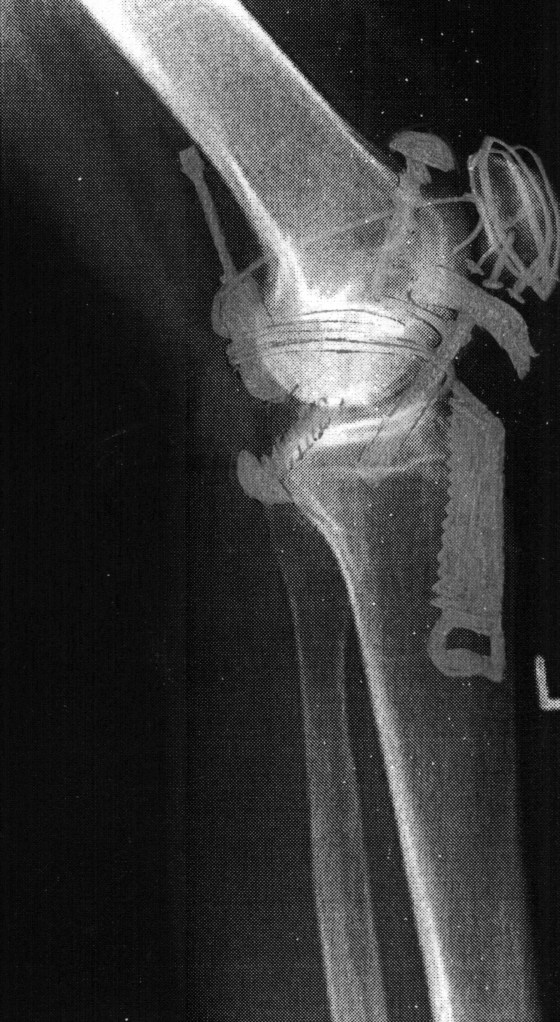

In der Geschichte in mehreren Tabs wäre darunter vermutlich die Szene, wie das Knie der Frau, zurück im Lande, aufgeschnitten und die Kniescheibe aus ihren drei Teilen wieder zusammengeflickt wird. Die Narkoseschwester ist hier ebenfalls Swingtänzerin und leiht der Frau für die OP ihren Discman (ein Jüngeren möglicherweise unbekanntes Device aus den 90ern), um das Hämmern und Bohren zu übertönen. Das Röntgenbild des Knies sieht nunmehr aus wie Mein kleiner Werkzeugkasten.